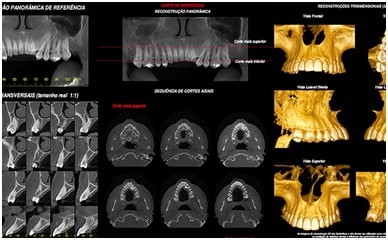

TOMOGRAFIA COMPUTADORIZADA

Exame Tridimensional dos Maxilares

Tomógrafo de Altíssima Resolução